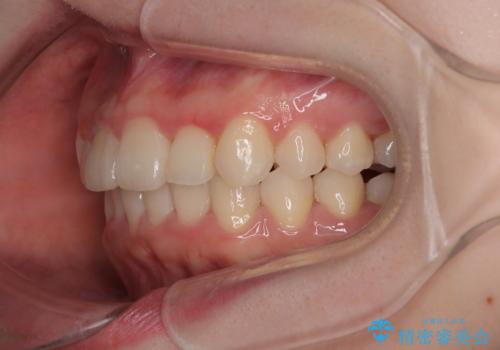

飛び出した前歯を引っ込める ワイヤー装置の非抜歯矯正

- 上下前歯のデコボコを気にして来院された患者様です。

マウスピースでもワイヤー装置でも対応可能でしたが、右側の咬み合わせが上顎がやや前方に位置していることから、補助装置を使用することが推奨されました。

自己管理の煩わしさを気にして、補助装置併用によるワイヤー装置での矯正治療を行うこととしました。

右上と左下の第一大臼歯2本が周辺の歯と比べて位置がずれていたため、ゴムかけやワイヤーに曲げを入れることで移動を試みましたが、どうよら癒着をしており、移動困難と判断されました。

見た目や咬み合わせに違和感がないとのことで、癒着歯の無理な移動は試みずに治療を終えることとしました。